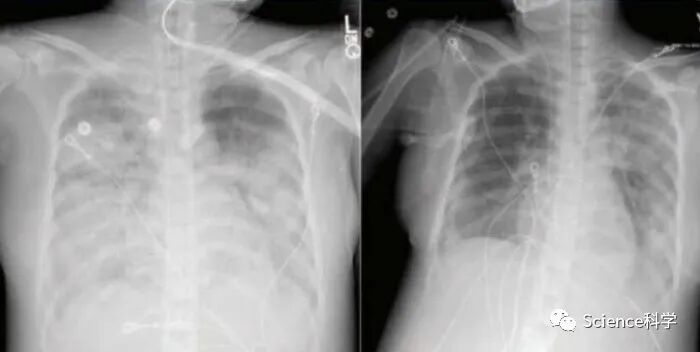

患者胸部CT检查结果

该患者在接受瑞德西韦治疗后,患者病情好转,减少呼吸机支持的需要,血氧水平和胸部CT检查结果好转。在入院治疗14天后,已经可以撤离机械通气。目前患者已出院,正在家中康复。